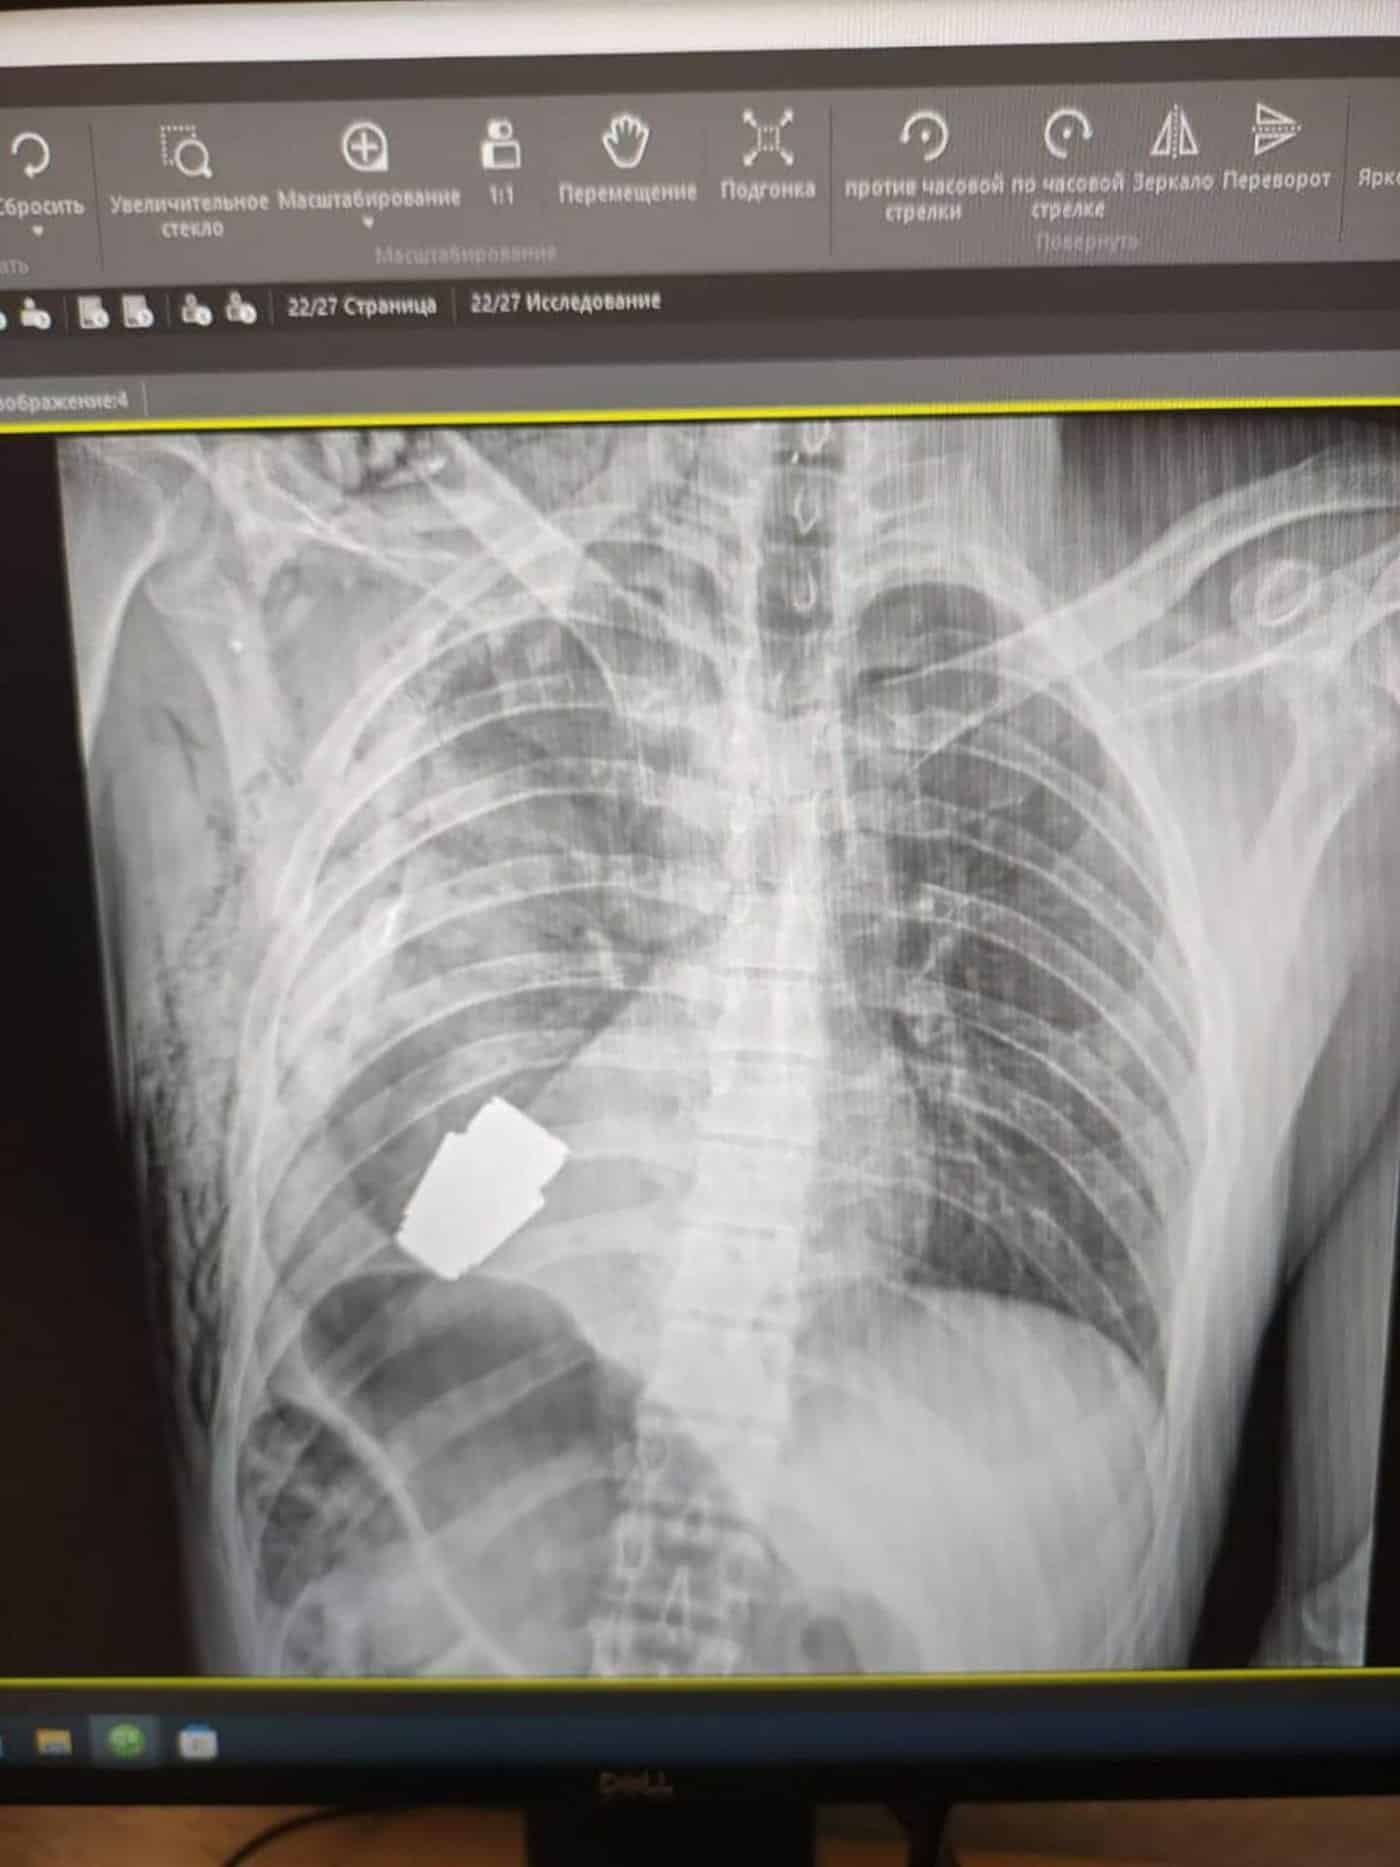

أظهرت الأشعة السينية القنبلة بالقرب من قلب الجندي

وأظهرت صورة بالأشعة السينية القنبلة ـ التي تطلق من قاذفة قنابل يدوية ـ بالقرب من قلب الجندي، فيما أظهرت أخرى جرّاحاً وهو يحمل العبوة المميتة داخل غرفة العمليات.